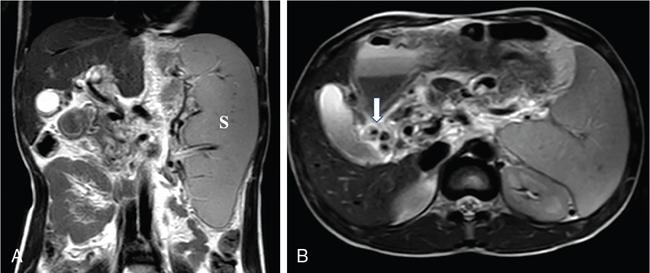

Kalpana Bansal, Poonam Narang The paediatric splenic abnormalities include both congenital and acquired pathological conditions. The congenital anomalies include variations in splenic number, location or fusion abnormalities and are more common than the acquired pathological conditions like splenomegaly, focal lesions, tumours and trauma. The splenic pathology can be evaluated with a wide variety of available imaging modalities including an ultrasound that is usually the first modality of choice in paediatric patients, computed tomography, magnetic resonance imaging and technetium-99m scintigraphy. The pattern-oriented approach to the radiological evaluation of splenic abnormalities may help to reach an accurate diagnosis and plan patient management. The congenital anomalies are common splenic abnormalities in paediatric patients. They usually result from absent or incomplete fusion of splenic lobules into one single organ before birth or abnormal location of the spleen. The congenital malformations include: The accessory spleen is commonly referred to as the splenunculus or supernumerary spleen. It results from the failure of the fusion of the primordial splenic buds in the dorsal mesogastrium during foetal life. The incidence is seen in 10%–30% of the population. The most common location of an accessory spleen is near the splenic hilum seen in about 75% of the cases and the pancreatic tail in 25% cases. It may be located anywhere along the course of the splenic vessels or in the abdomen and pelvis. The size of an accessory spleen ranges from few millimetres to centimetres and the number may vary from 1 to 6 (Fig. 9.21.1). The accessory spleens are usually asymptomatic and incidentally detected on imaging. But an accessory spleen present in an unexpected location can be misinterpreted as an abnormal soft tissue mass or lymph node. The characteristic imaging findings of the accessory spleen include similar imaging appearance to normal spleen on CT and MRI. The demonstration of feeding artery from the splenic artery can also be helpful in the differential diagnosis. Iron-containing MR contrast agents and Tc-99 sulphur colloid scintigraphy may be useful to confirm the diagnosis. The clinical significance of accessory spleen is seen in patients who had splenectomy for hypersplenism. In such patients, the accessory spleen may hypertrophy and result in recurrent disease; however, in patients of splenic trauma who had a splenectomy, it may help preserve the immune functions of the spleen. Splenopancreatic fusion is a rare anomaly that results due to abnormal fusion of splenic or pancreatic tissue as both organs arise from the dorsal mesogastrium close to each other. The ectopic splenic tissue may be located in the pancreatic tail (Fig. 9.21.2) and ectopic pancreas in the spleen or accessory spleen. It is also an incidental finding and asymptomatic. The clinical importance is to avoid complications during splenectomy or distal pancreatectomy. Splenogonadal fusion is an extremely rare anomaly that results due to the persistence of splenic tissue between the spleen and left testicle or epididymis. It may simulate masses and warrant unnecessary surgeries. The demonstration of splenic tissue connecting the spleen with the left gonad using any of the imaging modality helps in definitive diagnosis. Wandering or ectopic spleen is an extremely rare entity that results due to laxity or maldevelopment of the supporting splenic ligaments, and spleen can be found in any part of the abdomen. The incidence in several large studies of splenectomy is less than 0.5% and is mainly seen in children. The wandering spleen may be detected incidentally or present with different degrees of abdominal pain related to intermittent or acute torsion of the vascular pedicle. Ultrasound and CT remain the mainstay of diagnosis. Imaging findings include the absence of spleen in its normal position and a mass located anywhere in the abdomen or pelvis showing imaging and enhancement characteristics of normal splenic tissue. Besides, in the case of torsion, a typical ‘whirl’ pattern of the twisted pedicle and altered enhancement may also be demonstrated. Doppler shows absent flow within the spleen and low diastolic velocity with raised resistive index in the proximal splenic artery. The unenhanced CT shows hypoattenuation of the spleen, hyperdense intraluminal thrombus in the splenic artery and high density of the splenic capsule relative to parenchyma (‘rim’ sign). The contrast-enhanced CT shows absent or heterogeneous enhancement. The treatment modality of choice is splenopexy; however, splenectomy may be indicated in cases of infarction. Polysplenia and asplenia are typically seen in association with situs ambiguous or heterotaxia. Situs ambiguous with asplenia also known as Ivemark syndrome refers to right isomerism or bilateral right-sidedness and is characterized by an ambiguous location of abdominal organs with congenital absence of the spleen. It is more prevalent in males and associated with congenital heart disease in almost all cases (Fig. 9.21.3). Most patients die within the first year of life due to associated severe congenital heart disease and immunodeficiency due to absent spleen. Situs ambiguous with polysplenia is referred to as left isomerism or bilateral left sidedness. It is more common in females. The spleen may be located on the left or right side of the upper abdomen, the number may vary from 2 to 6 and diameter ranges from 1 to 6 cm (Fig. 9.21.4). The coexisting anomalies include a right-sided stomach, a midline or left-sided liver, bowel malrotation, short pancreas, absent gallbladder and associated inferior vena cava anomalies. Splenosis is an acquired anomaly that occurs following splenic trauma or splenectomy. It results due to auto-transplantation of splenic tissue usually in the peritoneal cavity but also may occur in extraperitoneal locations like the thoracic cavity. Splenosis is usually asymptomatic and incidentally detected on imaging. Splenosis is an acquired condition so it has distorted architecture and is supplied by surrounding vessels so, it can be mistaken for neoplastic lesions and lead to unnecessary surgery. A patient who had splenectomy for hypersplenism, splenosis may result in recurrent disease. However, a functioning splenic tissue may be required to preserve normal immunological function and remove old blood cells. Splenomegaly is a nonspecific finding seen as a manifestation of various disease processes listed in Box 9.21.1. CAUSES OF SPLENOMEGALY Ultrasound is usually the first and useful modality to evaluate enlarged spleen. It accurately measures the splenic span and also assesses the splenic echotexture, homogeneous or heterogeneous. Doppler USG is very good for the assessment of portal hypertension as a cause of splenomegaly by demonstrating flow in the splenoportal axis and collaterals. Both USG and CT also assesses the ancillary findings like lymphadenopathy in case of lymphoma or tuberculosis. Portal hypertension is one of the most common noninfectious causes of splenomegaly in children. Patients usually present with significant gastrointestinal bleed or massive splenomegaly. The causes of portal hypertension may be prehepatic, intrahepatic or posthepatic. The portal vein thrombosis is mostly idiopathic in children and results in collateral vessel development at porta known as cavernous transformation of the portal vein or portal cavernoma and portosystemic collaterals with massive splenomegaly (Fig. 9.21.5).